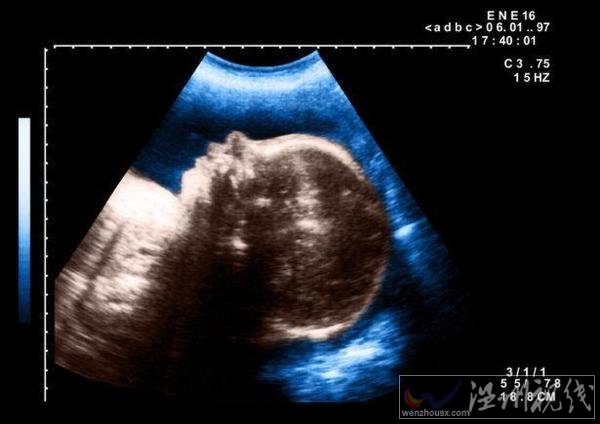

10月7日,埃及一名孕婦產下一個獨眼嬰兒,這個孩子在出生幾天后死亡。埃及嬰兒一只眼睛一時引起不少人關注,這名醫生猜測,可能是嬰兒在子宮內受到放射物影響導致的畸形。

據悉,當時這名醫生在被這個孕婦做檢查時,就發現她懷的這個孩子是一個嚴重畸形兒,但是沒想到會是這樣的。這個嬰兒出生時,只有一只長在中間的眼睛,在眼睛下面就是一張嘴巴。